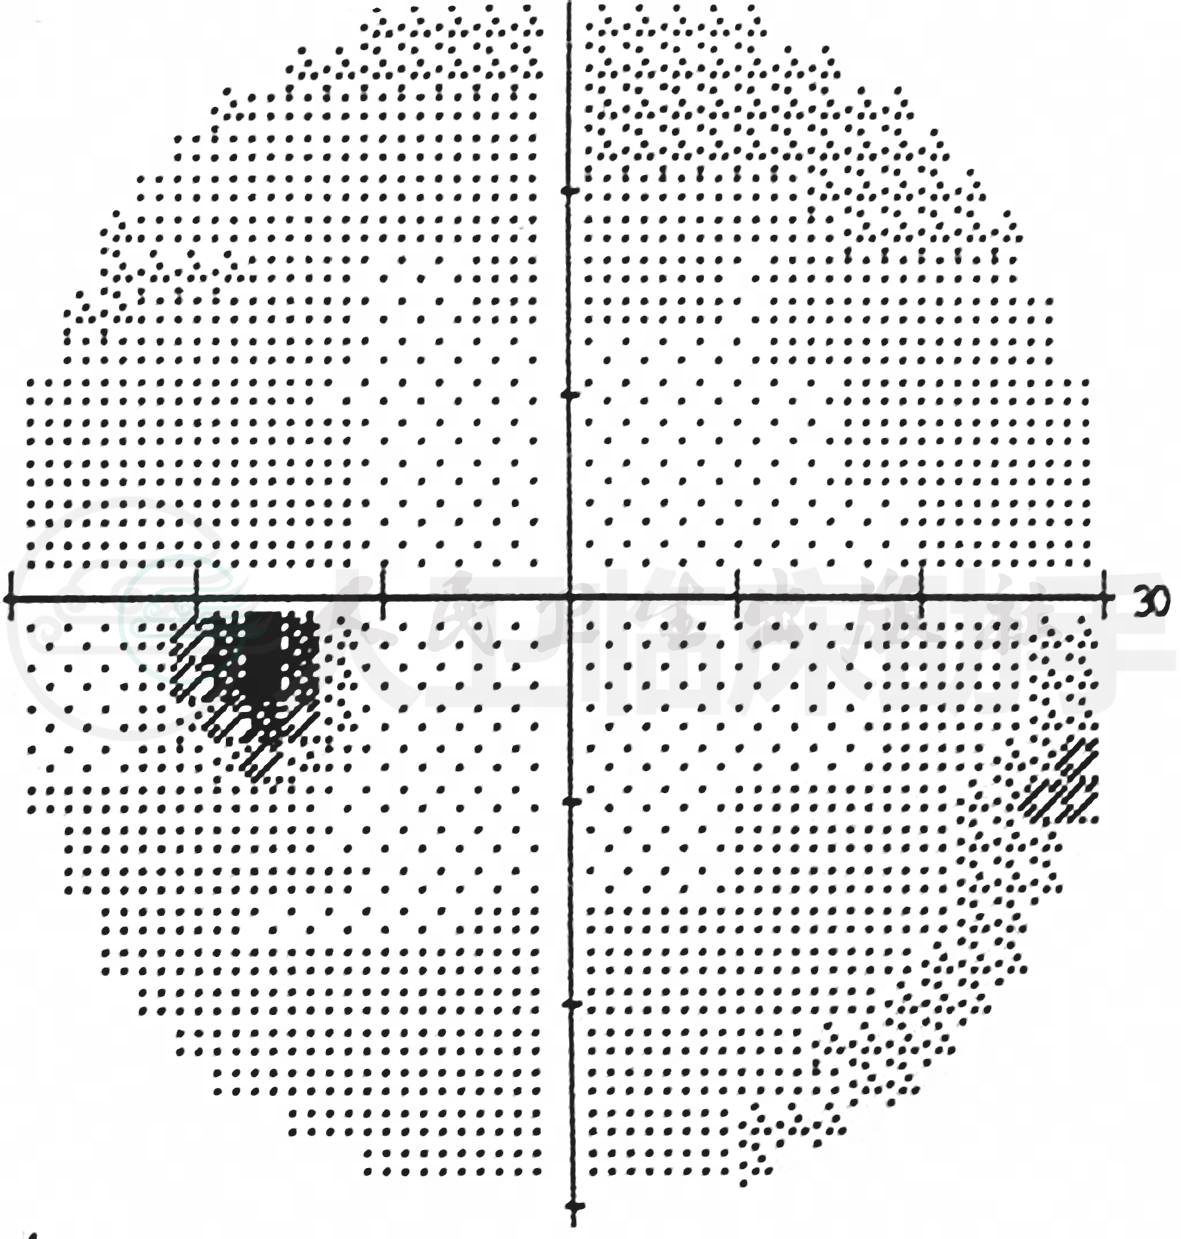

眼科检查:双外眼检查无异常。视力:右眼0.15;左眼0.15,矫正视力不提高。标准近视力表检查:双眼1.0/30cm。色觉检查不配合。双眼睑无肿胀,结膜未见明显充血,角膜透明,KP(-),前房深,房水清,虹膜纹理清。双眼瞳孔等大等圆,约4.5mm,双眼直接及间接对光反射灵敏。晶状体无混浊。眼底可见:双眼视盘界清色正,C/D约0.3。视网膜血管走形可,直径A/V约2∶3,黄斑区未见明显异常(图1)。患儿入院后,反复检测视力均为0.15。行PVEP、视野、mfERG检查均未见异常(图2)。

图2 视野检查未见异常